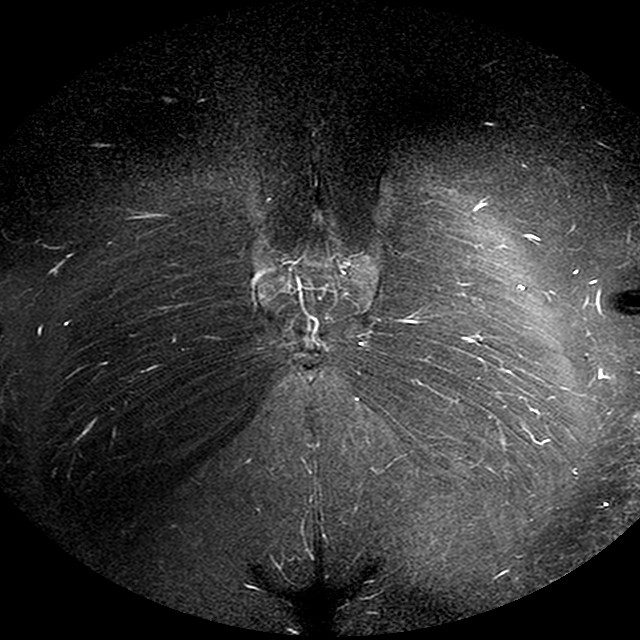

Esami: RMN BACINO

STIR

Evidenti e simmetriche alterazioni osteofitosiche in regione coxo femorale con riduzione delle rime articolari. Degenerazione completa del cercine glenoideo. Non attuali segni di versamento articolare. Non segni di edema osseo che escludono attuale algodistrofia od osteonecrosi. Lieve e simmetrica riduzione del trofismo della muscolatura glutea.